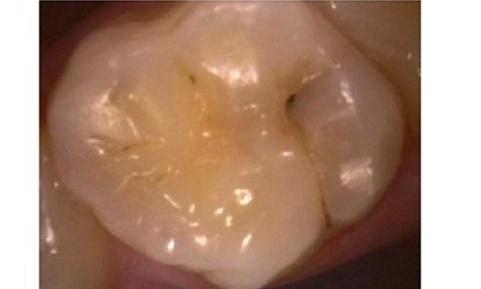

Smile Gallery: Tooth-Colored Dental Fillings

Before making a decision about any dental treatment, it's important to know that you're trusting your precious oral health and appearance to an experienced professional. Both Dr. Shahram and Dr. Sanati are passionate about delivering results that meet and exceed your expectations. Please take a look at the beautiful smiles of some of our patients and see for yourself!